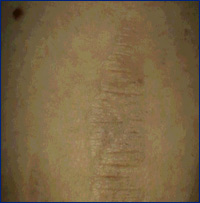

Outros usos incluem tratamento de estrias

(pré e pós tratamento,

8 sessões)